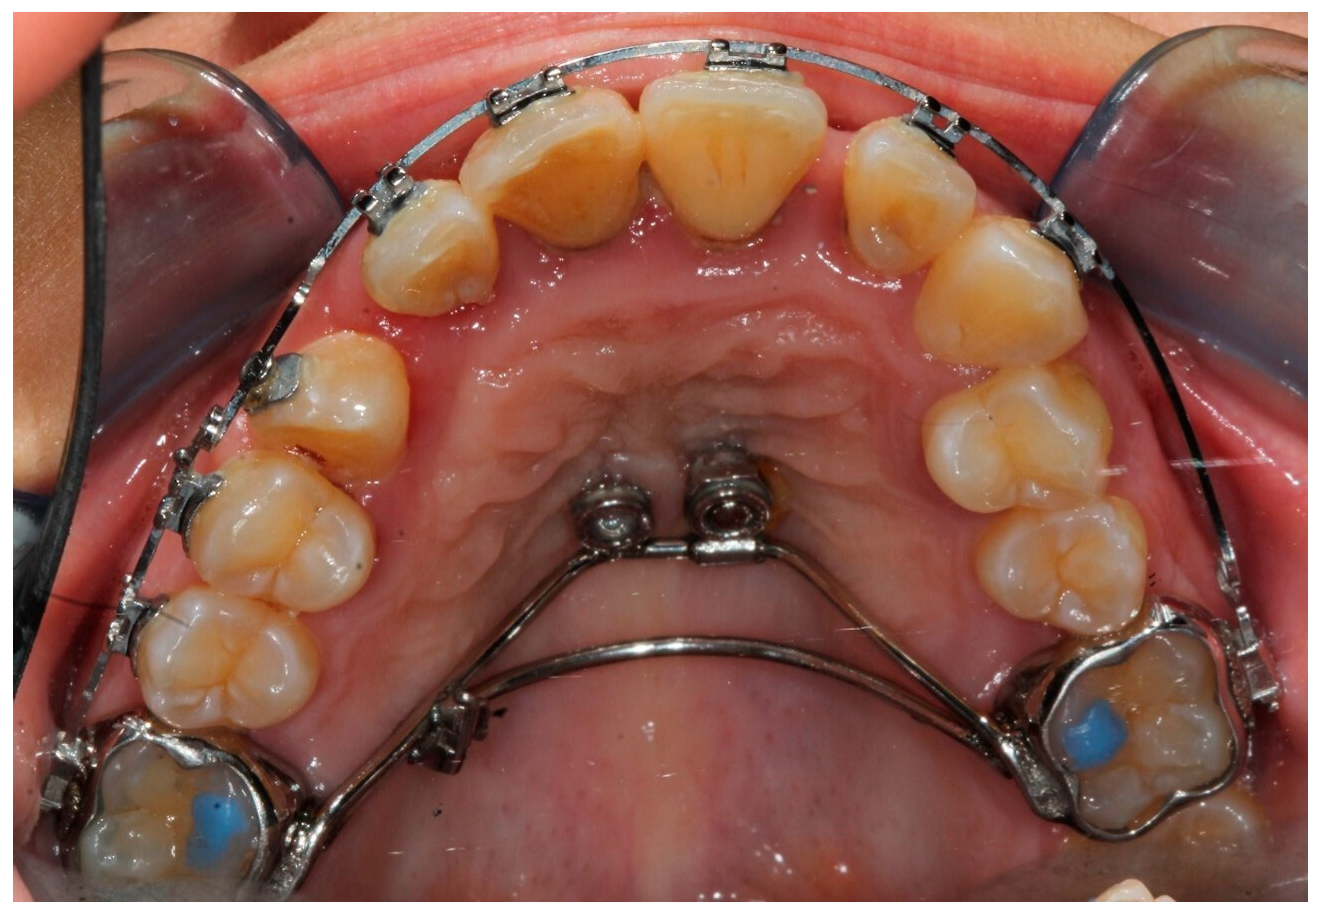

2. Case Report

- Annarumma, F.; D’Emidio, M.; Rodi, G.; Battista, G.; Papi, G.; Migliorati, M. The effectiveness of miniscrews in the three-dimensional control of a palatal impacted canine: “Canine Only” approach. Case report. Int. Orthod. 2021, 19, 716–725. [Google Scholar] [CrossRef]